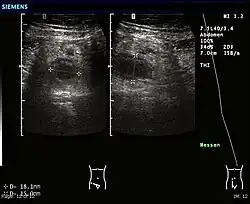

An ultrasound image of acute appendicitis in December 2008.

Abdominal ultrasonography, preferably with doppler sonography, is useful to detect appendicitis, especially in children. Ultrasound can show the free fluid collection in the right iliac fossa, along with a visible appendix with increased blood flow when using color Doppler, and noncompressibility of the appendix, as it is essentially a walled-off abscess. Other secondary sonographic signs of acute appendicitis include the presence of echogenic mesenteric fat surrounding the appendix and the acoustic shadowing of an appendicolith.[59] In some cases (approximately 5%),[60] ultrasonography of the iliac fossa does not reveal any abnormalities despite the presence of appendicitis. This false-negative finding is especially true of early appendicitis before the appendix has become significantly distended. Also, false-negative findings are more common in adults where larger amounts of fat and bowel gas make visualizing the appendix technically difficult. Despite these limitations, sonographic imaging with experienced hands can often distinguish between appendicitis and other diseases with similar symptoms. Some of these conditions include inflammation of lymph nodes near the appendix or pain originating from other pelvic organs such as the ovaries or Fallopian tubes. Ultrasounds may be either done by the radiology department or by the emergency physician.[61]